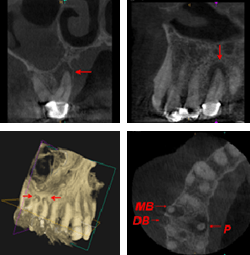

cone-beamCone Beam Computed Tomography (CBCT)

CBCT has proven to be an essential tool for successful diagnosis, treatment planning, and post-procedure monitoring for endodontic applications. With its accurate and high-quality 3-D representations of maxillofacial structures, CBCT technology offers tremendous improvements in diagnostic capabilities, eliminating surprises and minimizing the need for exploratory surgery. The result: more effective care and improved patient outcomes.